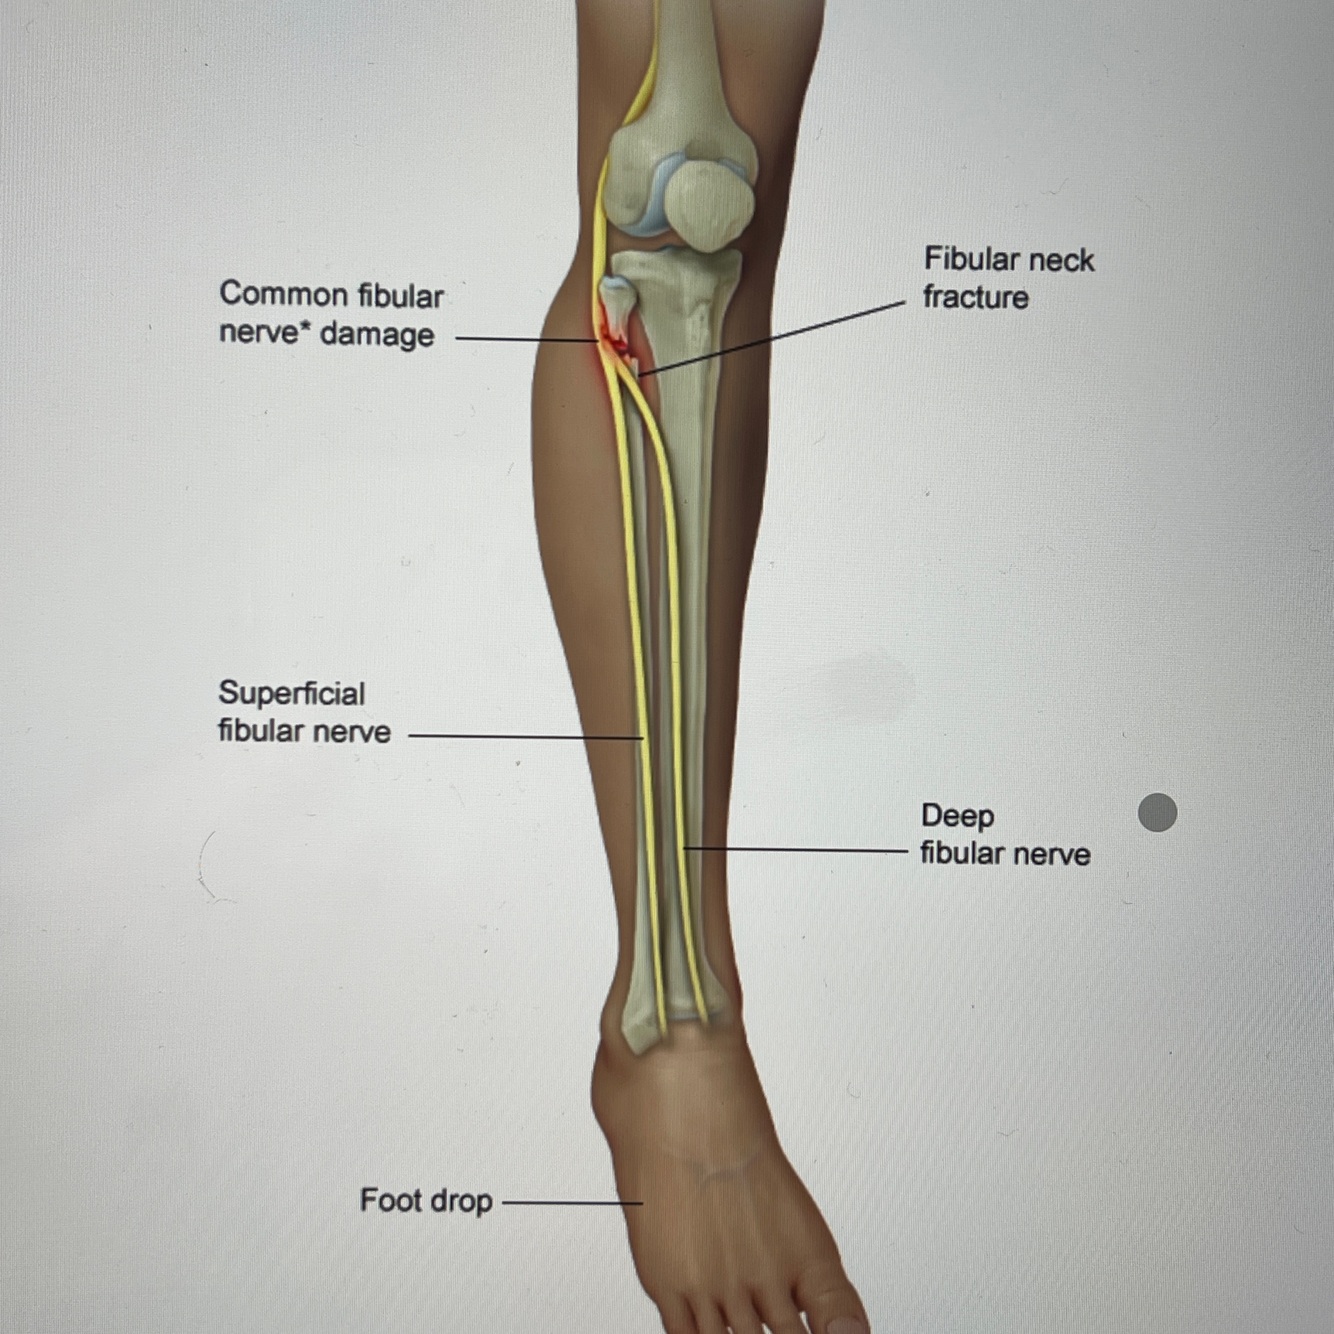

How well did you know this?